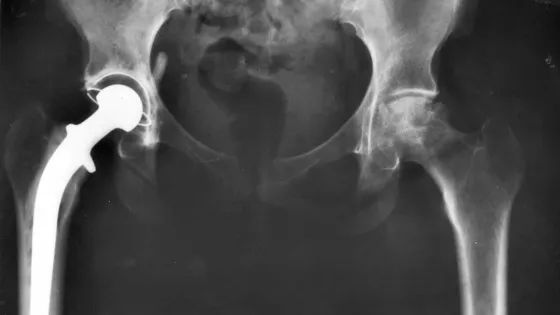

Обложка: Изображение из статьи. Рентген после эндопротезирования тазобедренного сустава / © NIADDK, 9AO4 (Connie Raab-contact), National Institutes of Health / Wikipedia